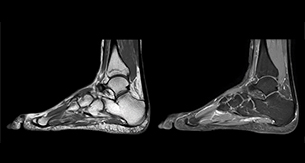

“In peripheral joints, mDIXON TSE imaging aids in diagnosing injuries in ligaments or tendons, for imaging degenerative and inflammatory pathologies such as osteoarthritis and rheumatologic disorders and for oncological exploration.”

“For tendon and ligament assessment around knee, ankle, hip and elbow, mDIXON TSE contributes to diagnostic confidence thanks to having images both with and without fat suppression – and without time penalty. This is possible because 2-point mDIXON is faster than the common 3-point Dixon method. It can also increase efficiency as it helps avoid having to add scans during the exam.”

Amazing quality of fat suppression

“In peripheral joints, we get good image quality in difficult areas with mDIXON TSE.

Fat suppressed images appear homogeneous over the entire image, even with large coverage at 3.0T – for instance in scapular or hip girdles – or in the bearing areas or around metal prostheses, where fat suppression is often deficient with STIR or spectral fat suppression, causing diagnostic difficulties. If a diagnostic image is right the first time, we don’t need to repeat or add a sequence.”

“mDIXON TSE sequences allow simultaneous characterization of morphological changes from the in-phase T2-weighted images and visualization of edematous changes, thanks to the water T2-weighted images from the same acquisition. Anatomical and morphological considerations could be a partial or complete ligament tear, a bony avulsion or hematoma.”